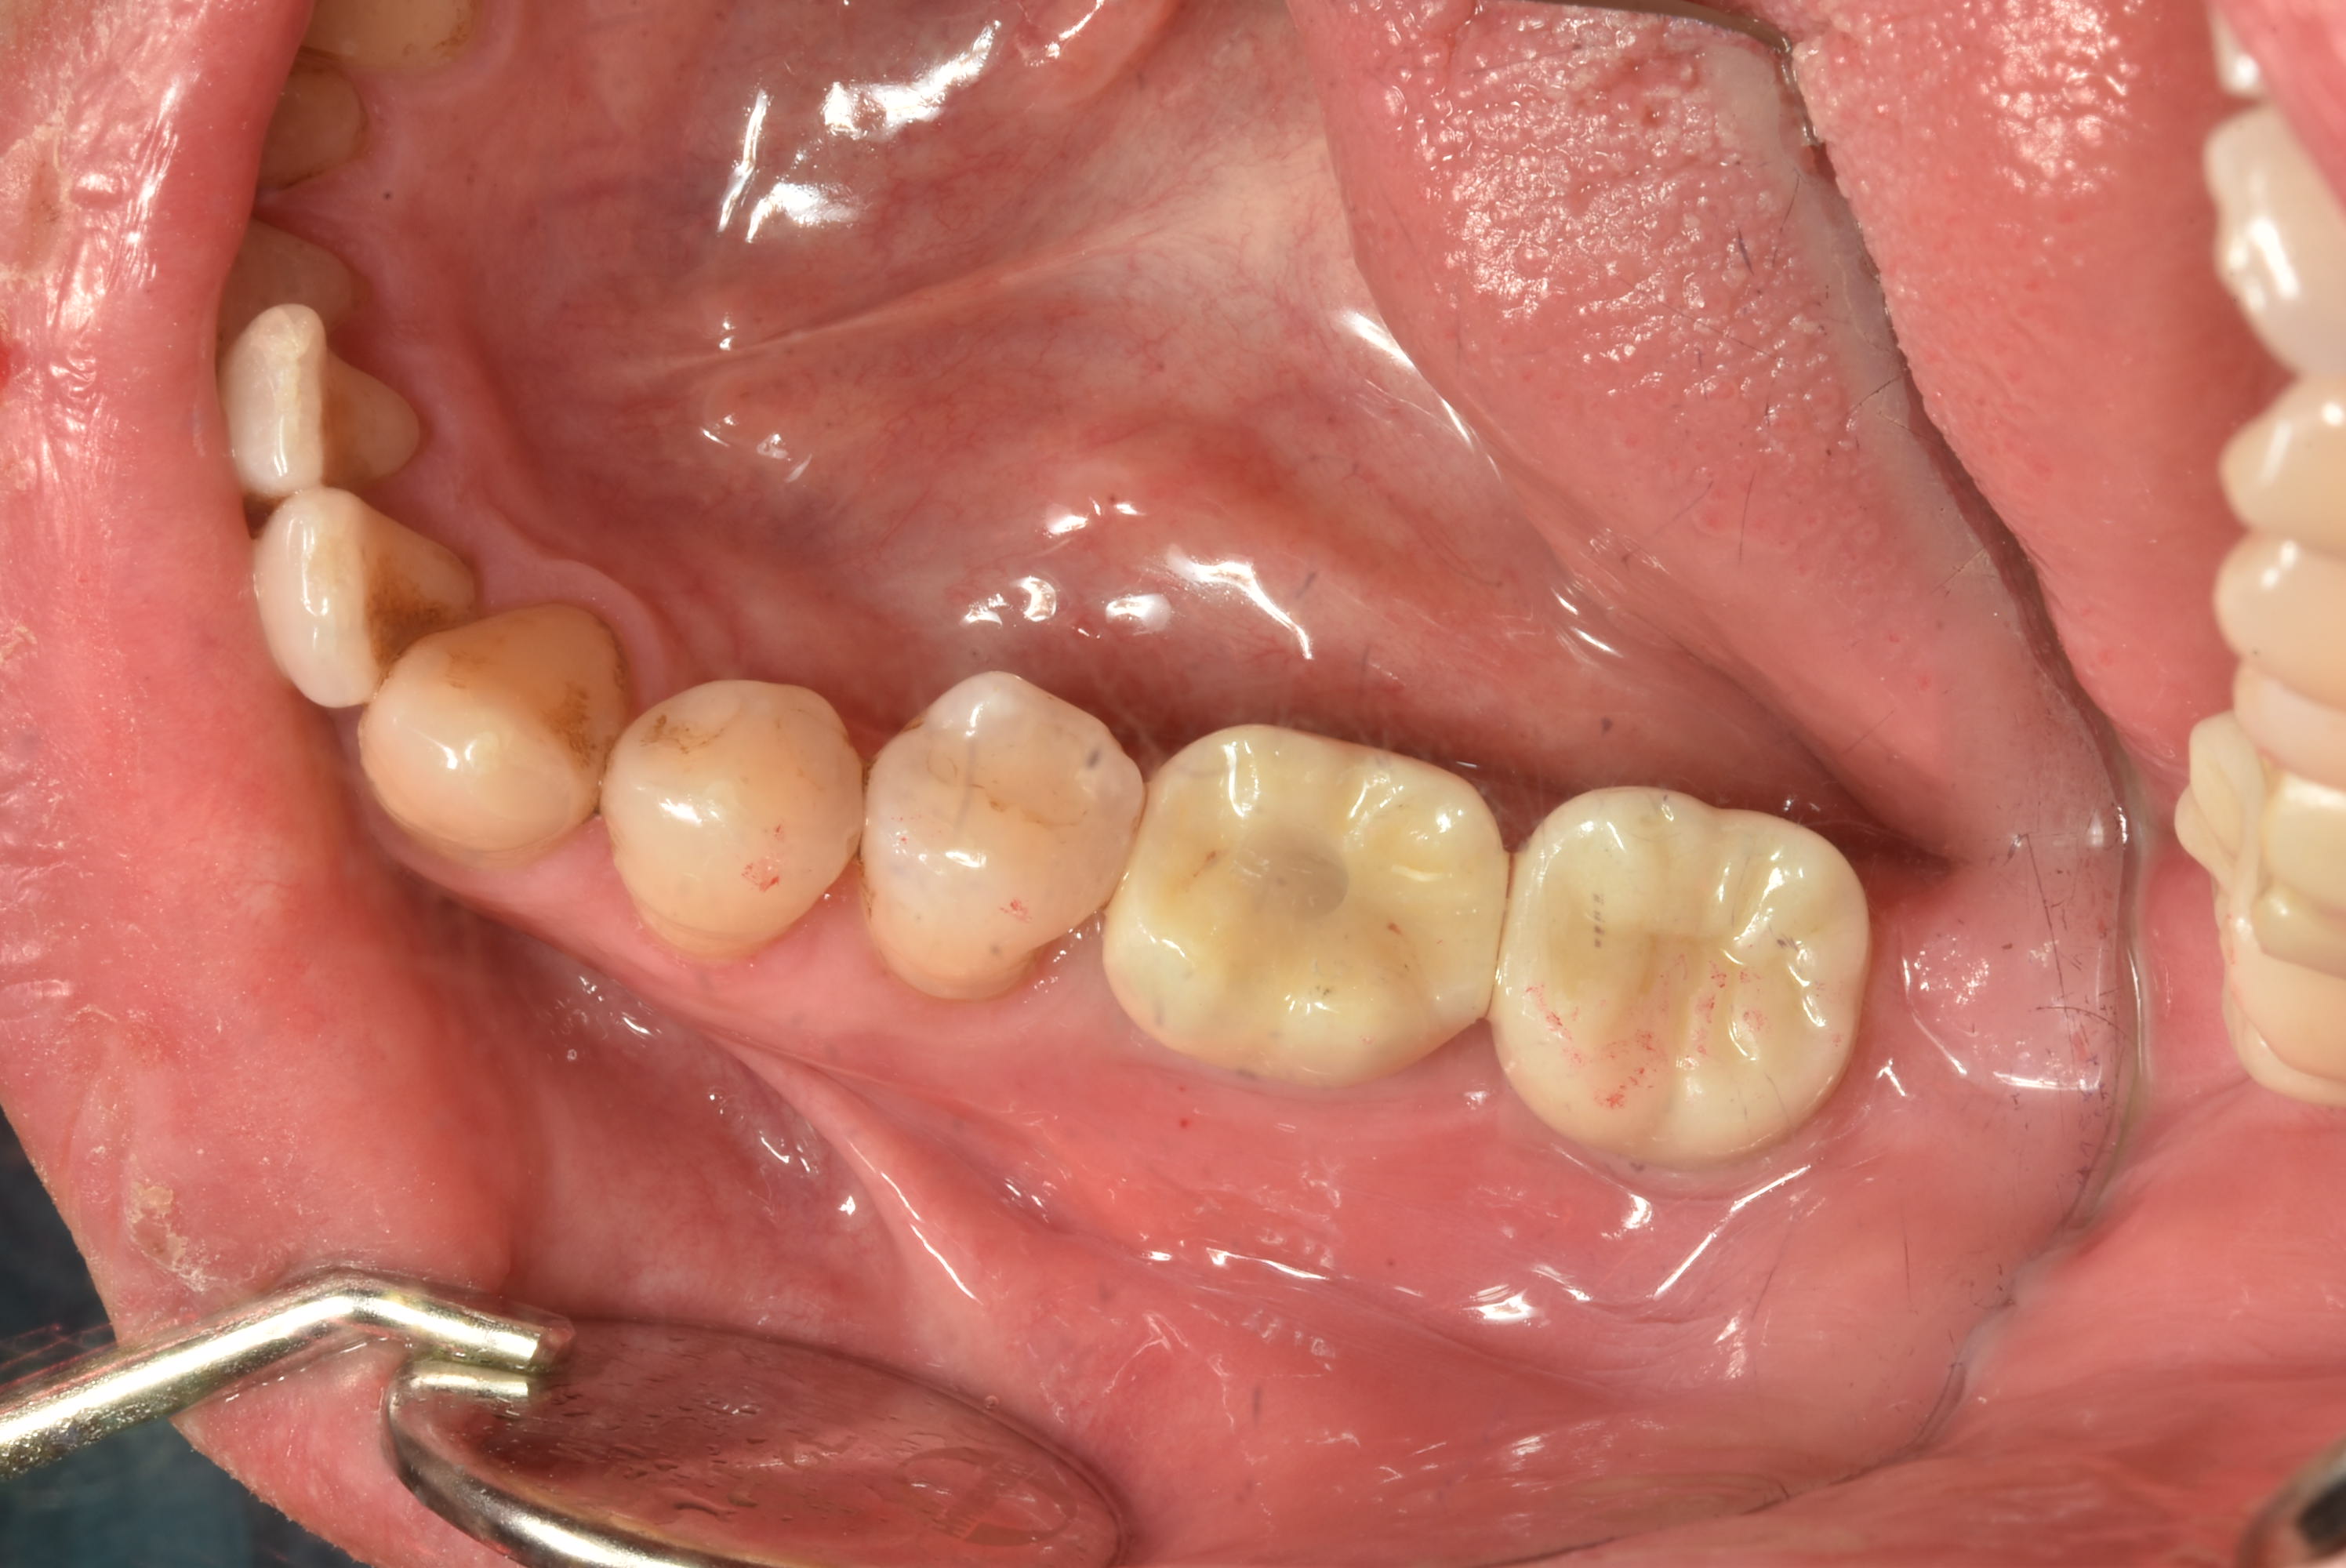

案例四

使用數年的假牙,牙根萎縮,建議拔除及植牙

醫生透過電腦斷層評估骨頭狀況決定植入的植體所放的寬度與深度

植入植體,並鎖上癒合螺帽

2-3個月癒合,7-10天完成假牙 ,試戴、調整咬合高度並鎖上,封填,完成